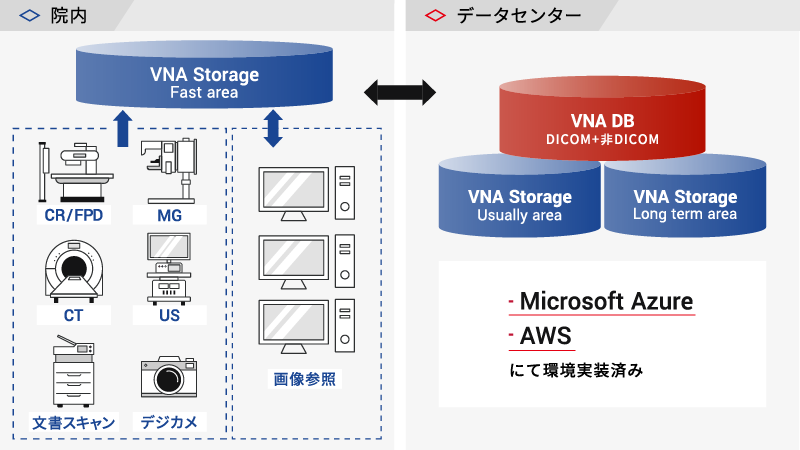

アーカイブ3層構造

アーカイブ3層構造

画像参照頻度を考慮し、ストレージ構造を高速・中速・低速とした3層データ管理を実現。

高価な高速ストレージの使用を最小限に抑え、全体的なストレージコストを効率的に管理しながら、必要なデータに迅速にアクセスできる環境を構築いたします。

オンプレ・クラウド版をラインアップ

オンプレ・クラウド版をラインアップ

医療機関様の環境、運営方針に合わせたシステム構成を準備いたします。

システム概要図